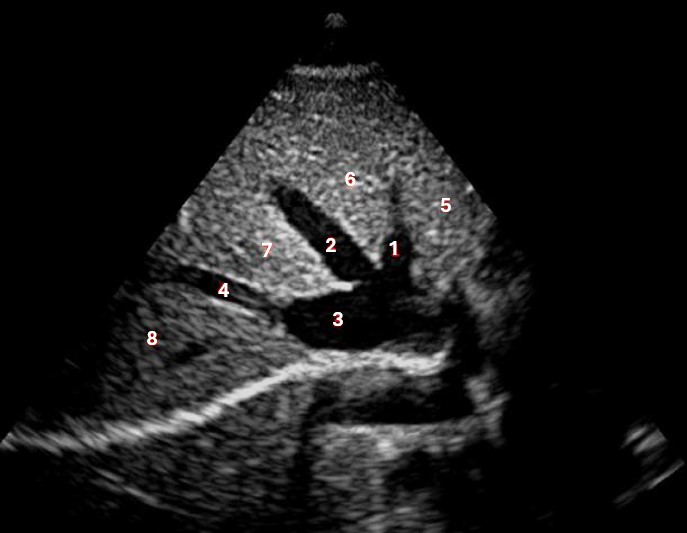

Which of the following structures is labeled number #1?

Left hepatic vein

What lobe of the liver is indicated by #1?

Posterior right lobe

Which of the following structures is labeled #2?

Middle hepatic vein

Which of the following structures is labeled #3?

IVC

Which of the following structures is labeled #6?

Medial left lobe

Which of the following structures is labeled #4?

Right hepatic vein

Which structure/vessel is indicated by #5?

Lateral left lobe

Which of the following structures is labeled #8?